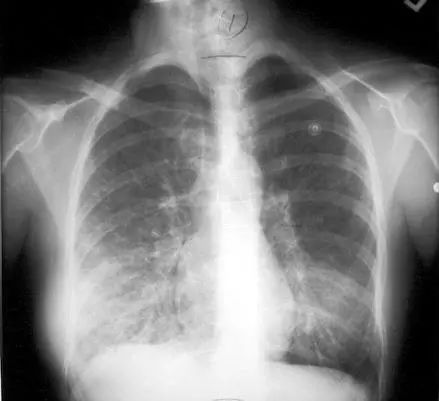

肺炎是指终末气道、肺泡和肺间质的炎症,可由细菌、病毒、真菌等多种病原体引起,典型症状包括咳嗽、咳痰、发热、胸痛等。